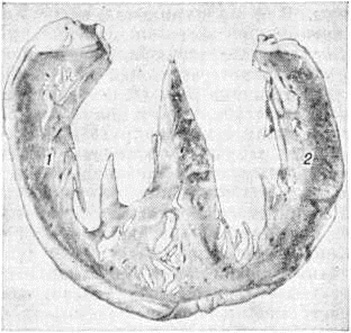

Особенности гипертрофии миокарда правого желудочка в значительной мере зависят от характера нарушений внутрисердечной гемодинамики. Объёмные перегрузки правого желудочка ведут к преимущественной гипертрофии его трабекулярного аппарата, в то время как собственно стенка значительно не утолщается. Перегрузки давлением обусловливают преимущественно гипертрофию собственно стенки правого желудочка наряду с гипертрофией трабекул (рисунок 1). Соотношение трабекулярно-папиллярного аппарата и собственно стенки может в определённой степени отражать соотношение перегрузок объёмом и давлением, существовавших при жизни больного.

Рис. 1.

Макропрепарат фронтального среза сердца при первичной лёгочной гипертензии (давление в правом желудочке до 180 миллиметров ртутного столба): наряду с трабекулярным аппаратом резко гипертрофирована стенка правого желудочка (1) — её толщина на отдельных участках превышает толщину стенки левого желудочка (2); верхушка сердца образована миокардом правого желудочка.